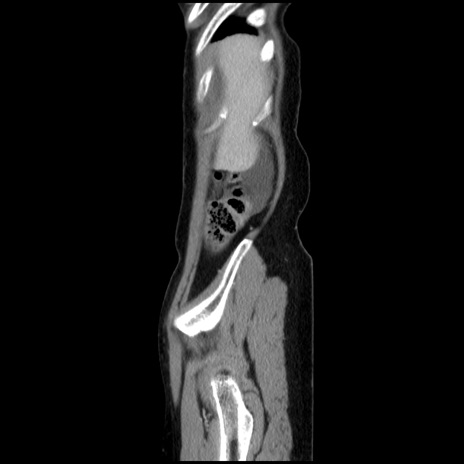

症例32(矢状断像)

【症例】40歳代 女性

【主訴】上腹部痛、嘔気・嘔吐

【現病歴】約9時間前頃から急に上腹部痛、嘔気、嘔吐が出現。改善しないため救急要請。

【既往歴】子宮頚癌(広汎子宮全摘術、放射線療法)、腸閉塞

【身体所見】腹部:平坦、軟、腸雑音亢進、上腹部を中心に腹部全体に圧痛あり。

【データ】WBC 8400、CRP 0.03